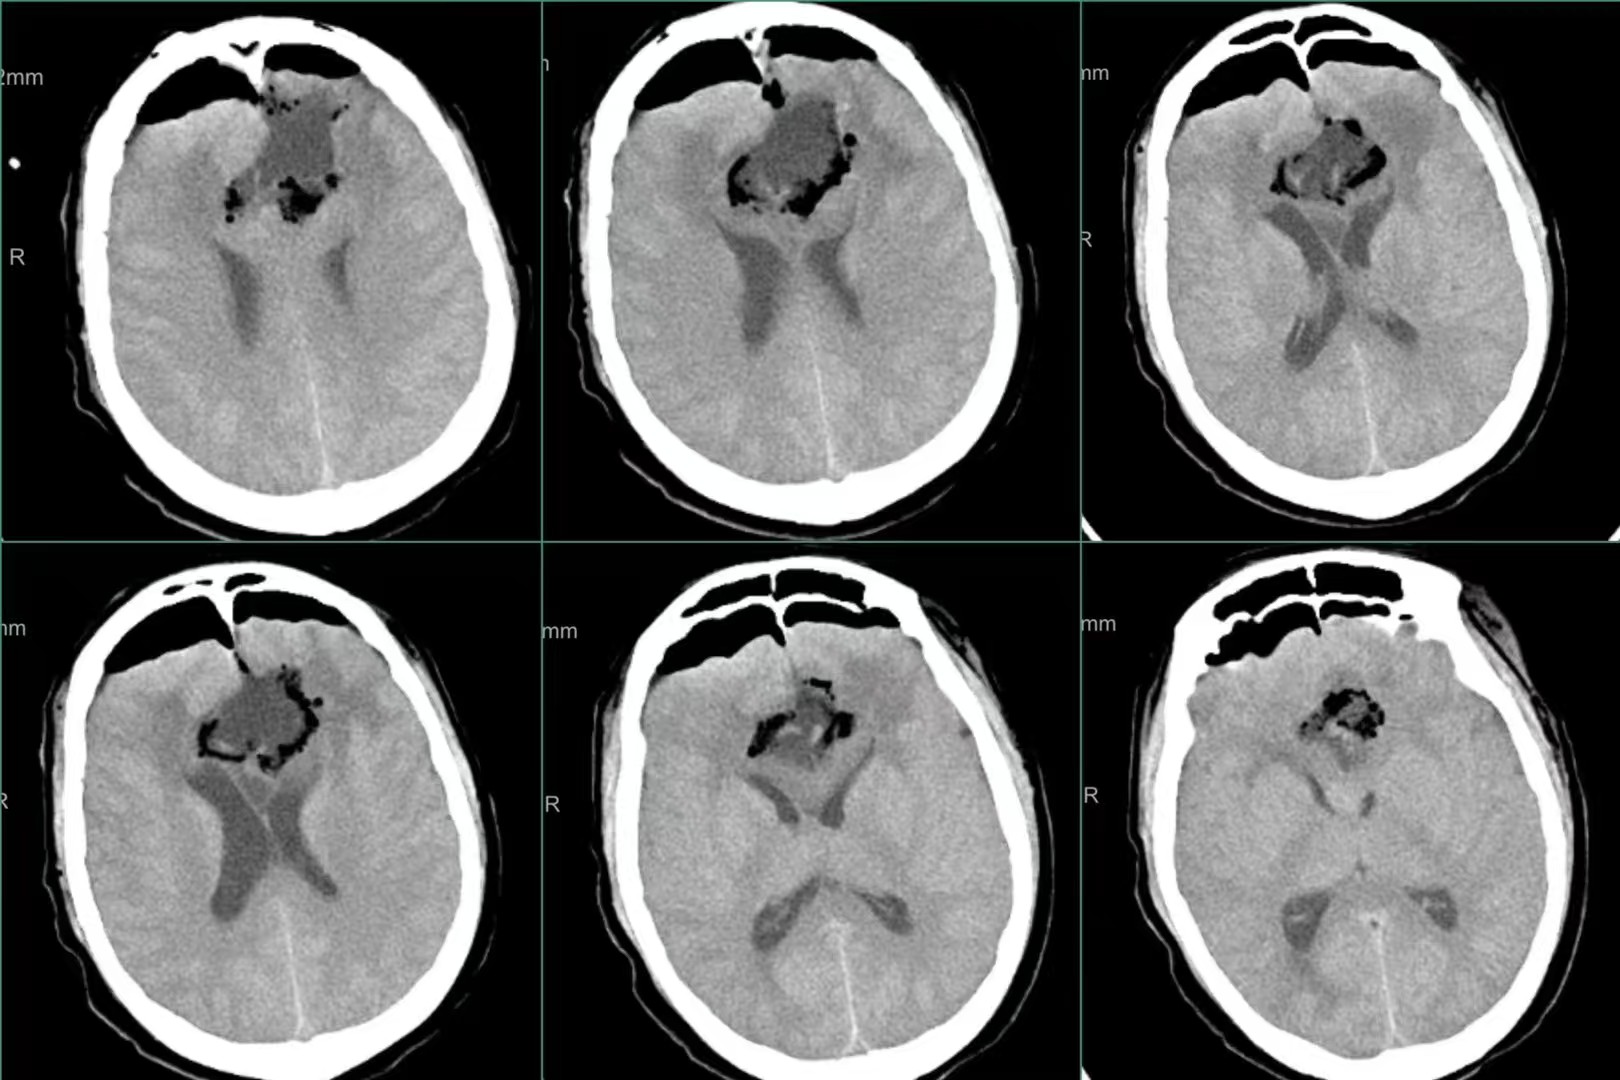

巨大蝴蝶型胶质母细胞瘤(Butterfly glioblastomas)切除术

患者,女性,58岁,因“反应迟钝、记忆力下降1月,加重伴头痛、恶心、呕吐1周”入院。